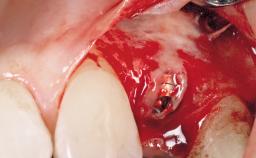

Late Flapless Placement of an Implant in a Maxillary Left Central Incisor Site

A 39-year-old male patient presented with a chief complaint of discomfort and gingival discoloration around his maxillary left central incisor. He was in good general health and was a non-smoker. His past dental history was significant because of the traumatic fracture of tooth 21 in a sporting accident at age 13. Initial dental treatment included endodontic therapy and a full-coverage restoration. The patient became symptomatic 5 years later, when structural failure of the tooth resulted in the dislodgment of the crown. Endodontic retreatment, apical surgery, and post-and-core restoration were performed.

| Bone Augmentation | Horizontal|Staged |

| Augmentation Materials | Xenogenous|Membrane |

| Bone Volume | Deficient horizontally, requiring prior grafting |